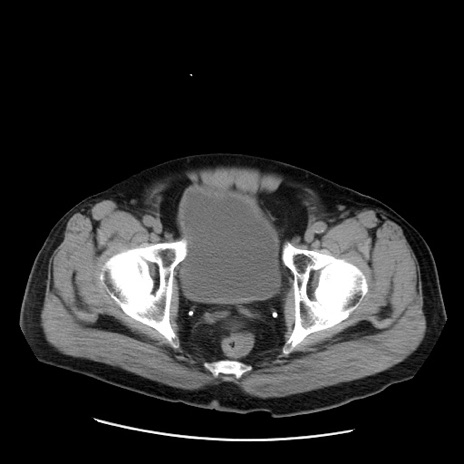

症例20(横断像)

【症例】 60歳代男性

【主訴】 腹部膨満、嘔吐

【現病歴】5日前頃より倦怠感を認め食事量減少し4日前の朝嘔吐、食事摂取困難となった。 3日前近医受診し点滴施行され整腸剤などを処方された。 当日他院を受診し、腹部膨満著明、炎症反応の上昇(CRP10.8、WBC11200)あり、紹介受診となる。

【身体所見】 意識JCS1 受け答えがはっきりしないBP 111/57mHg、 P 67bpm、、BT35.2°C、SpO2 97%(RA)、 腹部:膨隆、打診で鼓音あり、全体的に圧痛有り、腸蠕動音(-)、反跳痛ははっきりせず。

【データ】WBC 11400、CRP 14.20